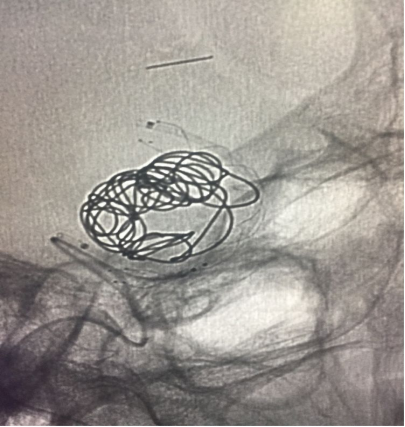

因为要给患者省钱,准备密网支架十动脉瘤内弹簧圈疏松填塞,先在动脉瘤流出道放一圈作为支柱支撑

然后释放支架并开始在动脉瘤流入道填塞弹簧圈